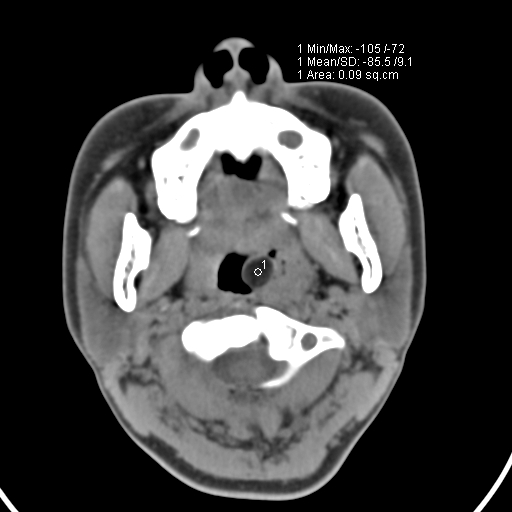

以下是引用zjzjr在2008-12-5 11:46:00的发言:[br]脂肪密度,壁有钙化.考虑口咽部皮样囊肿可能性大.双侧上颌窦炎,双侧下鼻甲粘膜肥厚.增殖腺肥大,扁桃体亦增大,考虑炎性.

以下是引用随光逐影在2008-12-5 18:27:00的发言:[br]1)考虑左侧茎突过长综合征并茎突舌骨韧带囊肿形成突入咽部;左侧咽部慢性炎症。2)鼻咽腺样体肥大。3)双侧扁桃体肿大。4)双侧上颌窦炎。5)双侧下鼻甲粘膜肥厚。